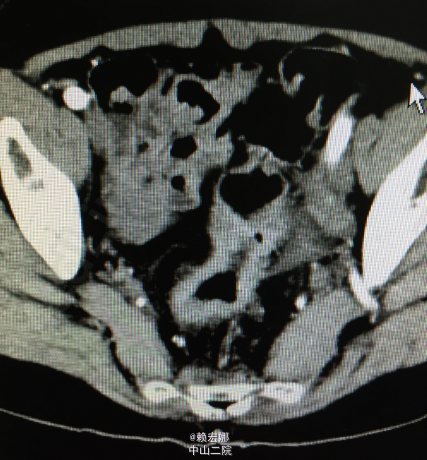

外院肠镜:距肛门口5-15cm直肠环周菜花状物,质地脆,易出血,近端可见多发小息肉。外院病理提示直肠癌,予以洛铂+氟尿嘧啶+左亚叶酸钙两次化疗,化疗过程顺利。我院CT:1、直肠中上段及乙状结肠远端肠管管壁不均匀增厚,管腔稍狭窄,可符合直肠癌改变;邻近淋巴结肿大,考虑为转移性;2、肝内多发类圆形低密度影,考虑囊肿;3、左肾多发低密度影,考虑囊肿可能性大;4、腹主动脉及双侧髂动脉硬化;5、心腔密度减低,考虑贫血。